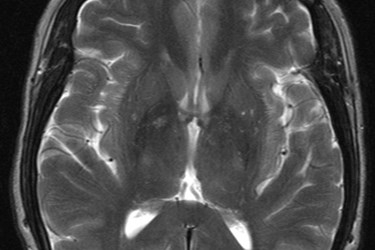

Image Credit: "MRI T2 Brain axial image." Afiller. CC BY-SA 3.0: http://creativecommons.org/licenses/by-sa/3.0/